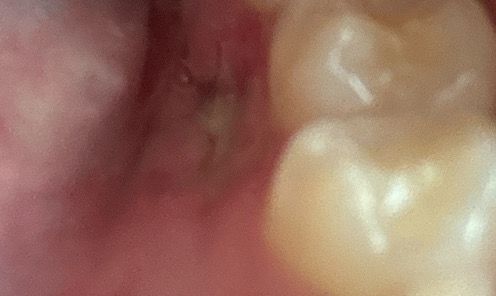

과잉치 수술 5일차!! 실밥 몇개 풀었는데 질문있어요!

제가 되게 걱정이 많거든요 오늘 아랫니 혀쪽 과잉치 빼고 뼈이식까지 한지 5일차거든요 어제는 실이 풀려서 병원가서 실 1개 빼고 다 뺏거든요? 근데 원래 느낌이 혀로 한번 만져보면 안으로 들어가있는 느낌이 드나요?? 시간이 지나면 잇몸이 차올라서 빈 느낌이 드는건가요?? 궁금해요

안에 있던 과잉치가 제거되면서 오목하게 들어가는데요. 안에서부터 피가 차올라 뼈와 잇몸이 생기기 때문에 겉에있는 조직이 일부 괴사되고 꺼져서 혀로 건드렸을 때 오목하게 들어갔다고 느껴집니다. 겉의 잇몸은 1개월 정도, 안쪽 뼈는 3개월 정도 지나면 다 아물기 때문에 시간이 지나면 예전처럼 매끈해지게

될테니 너무 걱정하지 않으셔도 되겠습니다.

과잉치를 발치하고 나면 해당 부위에 빈 공간이 생기기 때문에 움푹 파이는 것 같은 느낌이 들 수 있습니다. 골 이식까지 했다면 시간이 지나면서 뼈가 차오르기 때문에 해당 부위는 단단한 뼈로 대체되게 됩니다.

혀로 자극을 하거나 하면 골이식가 제대로 아물지 못하게 되어 감염 등이 일어날 수 있으니 가능하면 해당 부위를 자극하지 않는 것이 좋습니다.